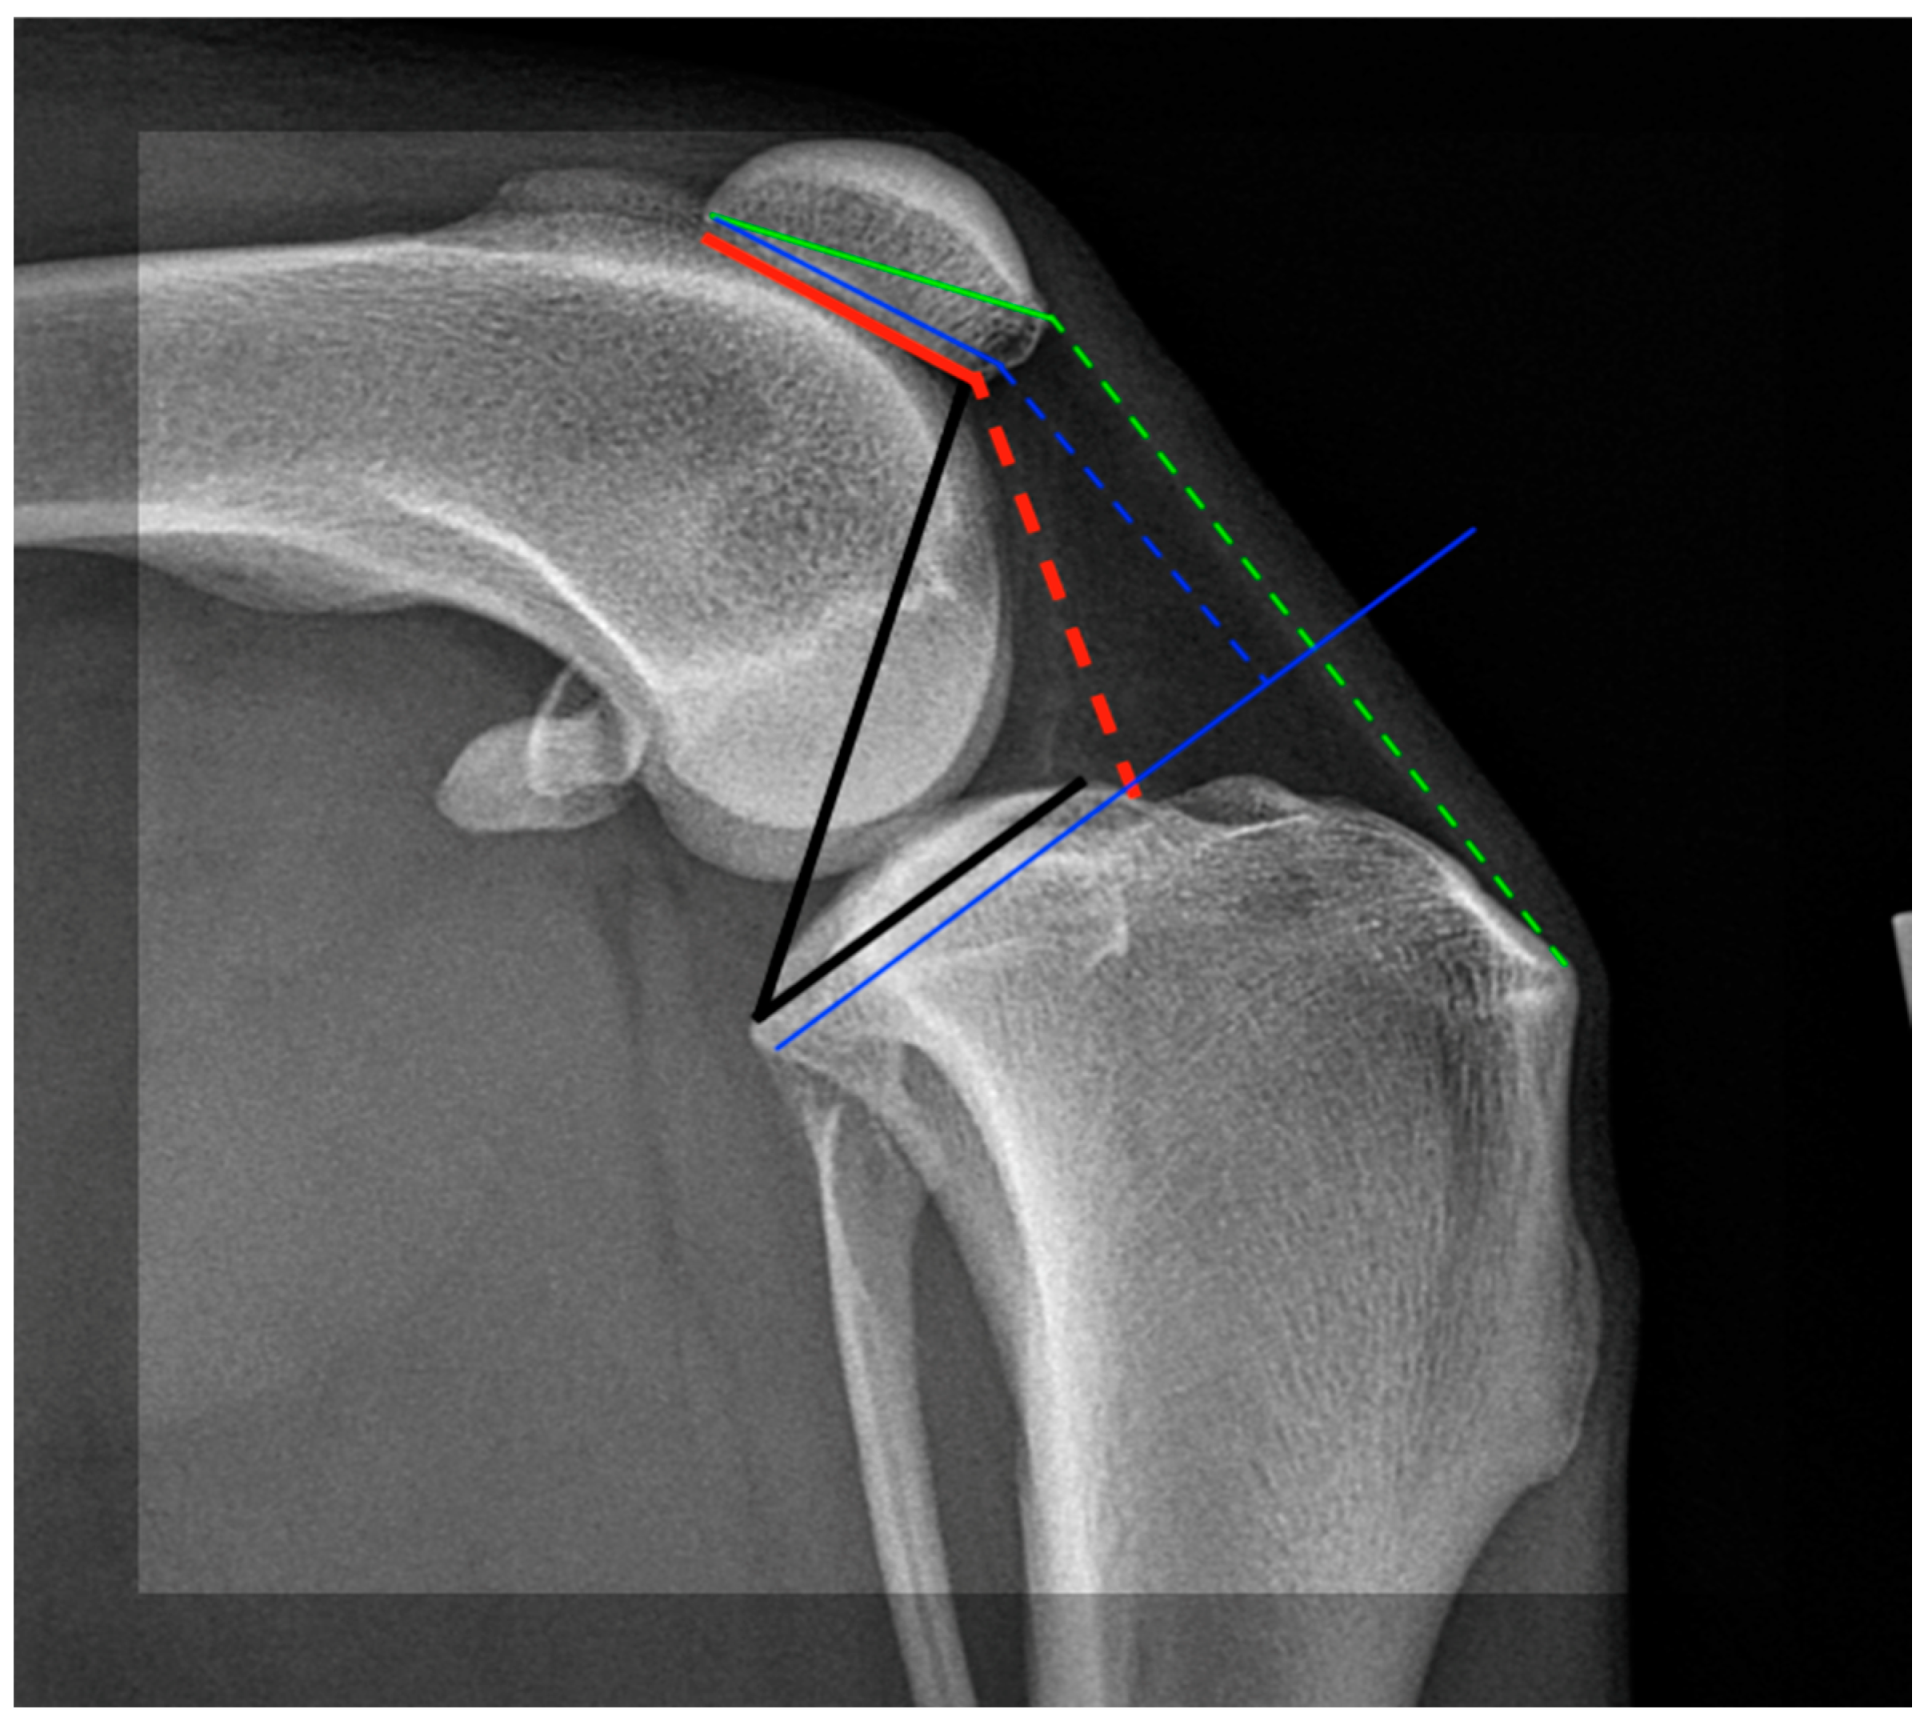

- Bonadio, M.B.; Torres, J.A.P.; Filho, V.M.; Helito, C.P. Plateau-patella angle: An option for assessing patellar height on proximal tibia osteotomy. Acta Orth. Bras. 2016, 24, 127–130. [Google Scholar] [CrossRef] [PubMed][Green Version]

- Lorinson, K.; Kneissl, S.; Tichy, A.; Lorinson, D. Radiographic Measurement of the Patellar Height in Cats Using the Tibia Plateau-Patella Angle (TPPA). Biomed. J. Sci. Tech. Res. 2023, 49, 40929–40933. [Google Scholar]

- De Carvalho, A.; Andersen, A.H.; Topp, S.; Jurik, A.G. A method for assessing the height of the patella. Internat. Orthop. 1985, 9, 195–197. [Google Scholar] [CrossRef]